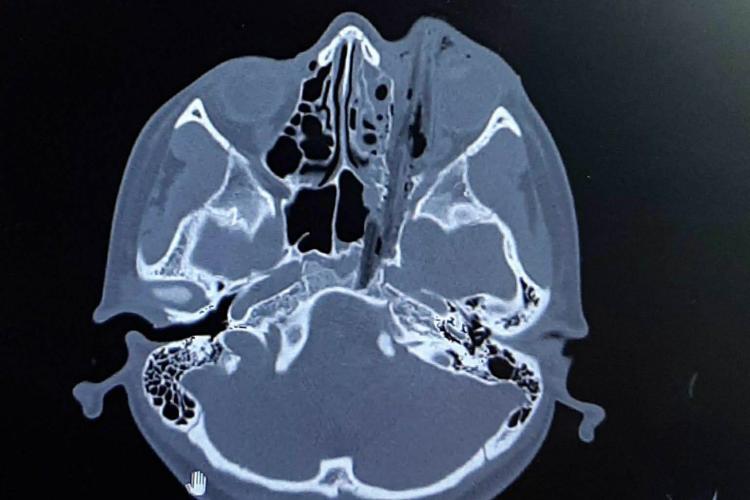

Случай, с которым они работали, был очень трудным: 10-летняя девочка во дворе дома упала лицом на клумбу. Сухой замерзший стебель растения проткнул ей глазницу, прошел через носовые пазухи и чуть-чуть не дошел до жизненно важных органов.

В офтальмологической больнице достали части стебля со стороны глазницы. В областной больнице удалили обломки из основания черепа – эндоскопическим способом, через нос.

Такие операции считаются вмешательством наивысшей категории сложности.